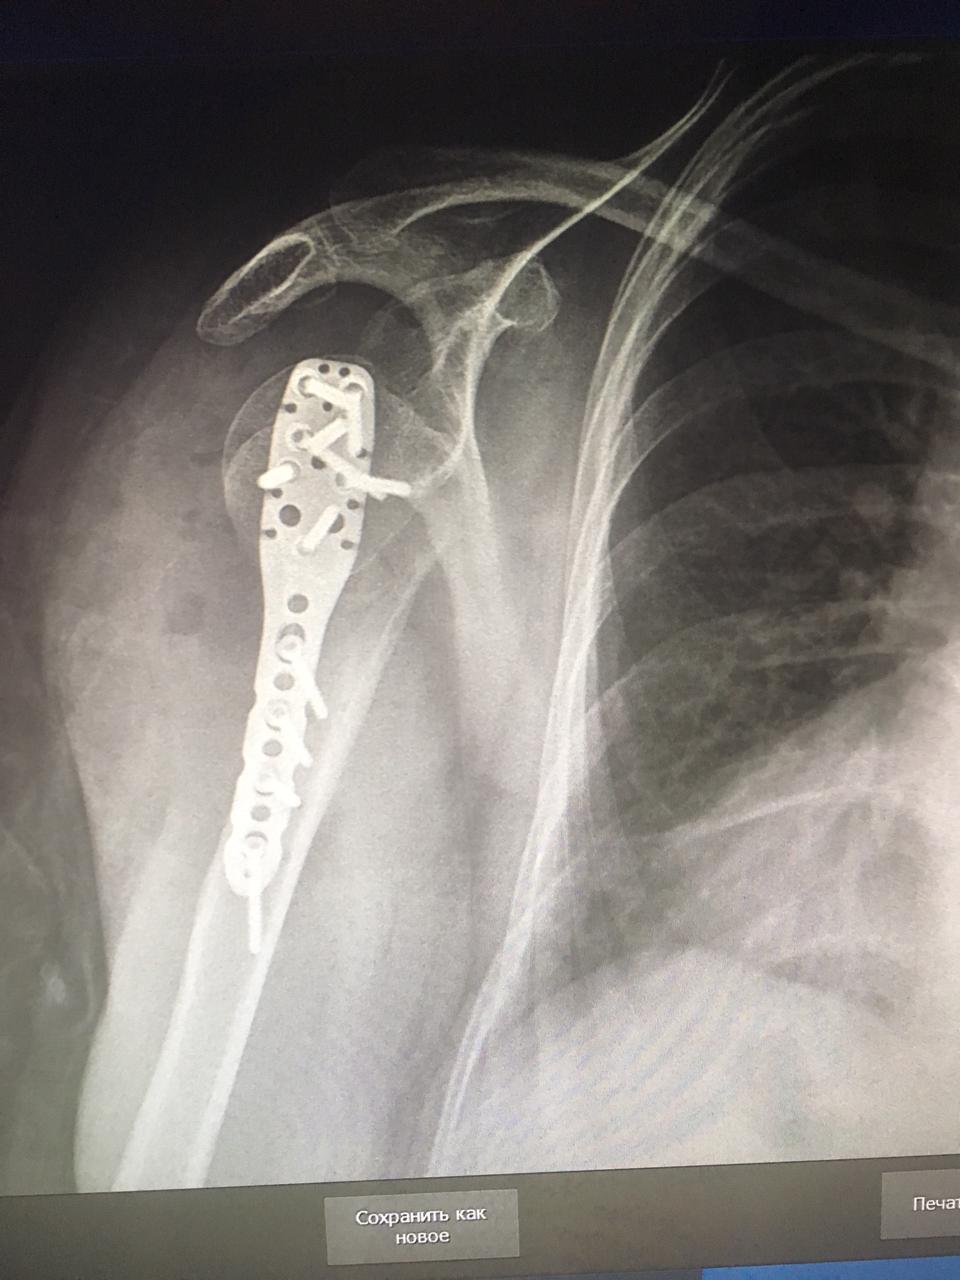

02.06.2021 жылы Жалағаш аудандық ауруханасына Ербол Аяна Ғалымжанқызы 2015ж.т. жедел хирургия бөліміне түсті. Науқасқа жедел түрде бөлім меңгерушісі М.Оспанов пен травматолог дәрігері Ж.Сыдықовтың қатысуымен "Электронды рентген аппараты бақылауымен жабық орнына келтіру, спица арқылы бекіту отасы" жасалды. Ота жасалған науқастың түскен кездегі диагнозы: Сол жақ иық сүйегі айдаршығының жабық ығысқан сызығы. Науқастың қазіргі отадан жағдайы қанағаттанарлық, шағымы жоқ.